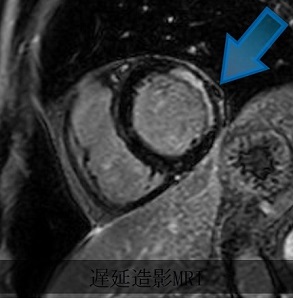

遅延造影

心筋梗塞例、白い部分が傷害を受けた心筋

心臓の画像検査の中では比較的新しい分野で、X線を用いず心筋の状態をより詳細に評価することができます。また、ガドリニウム造影剤を用いることで、心筋の血流を評価したり、心筋のダメージや線維化を目に見える形で描出することができます(遅延造影)。またT1マッピングでは、造影検査だけでは把握が困難な心筋の発症や線維化も捉えることができます。それにより、心不全の原因の特定などに役立てられます。さらに、造影剤を用いずに心臓の動きや心臓の血管の詰まりや狭窄を評価することができます(シネ動画、MRアンギオ)。